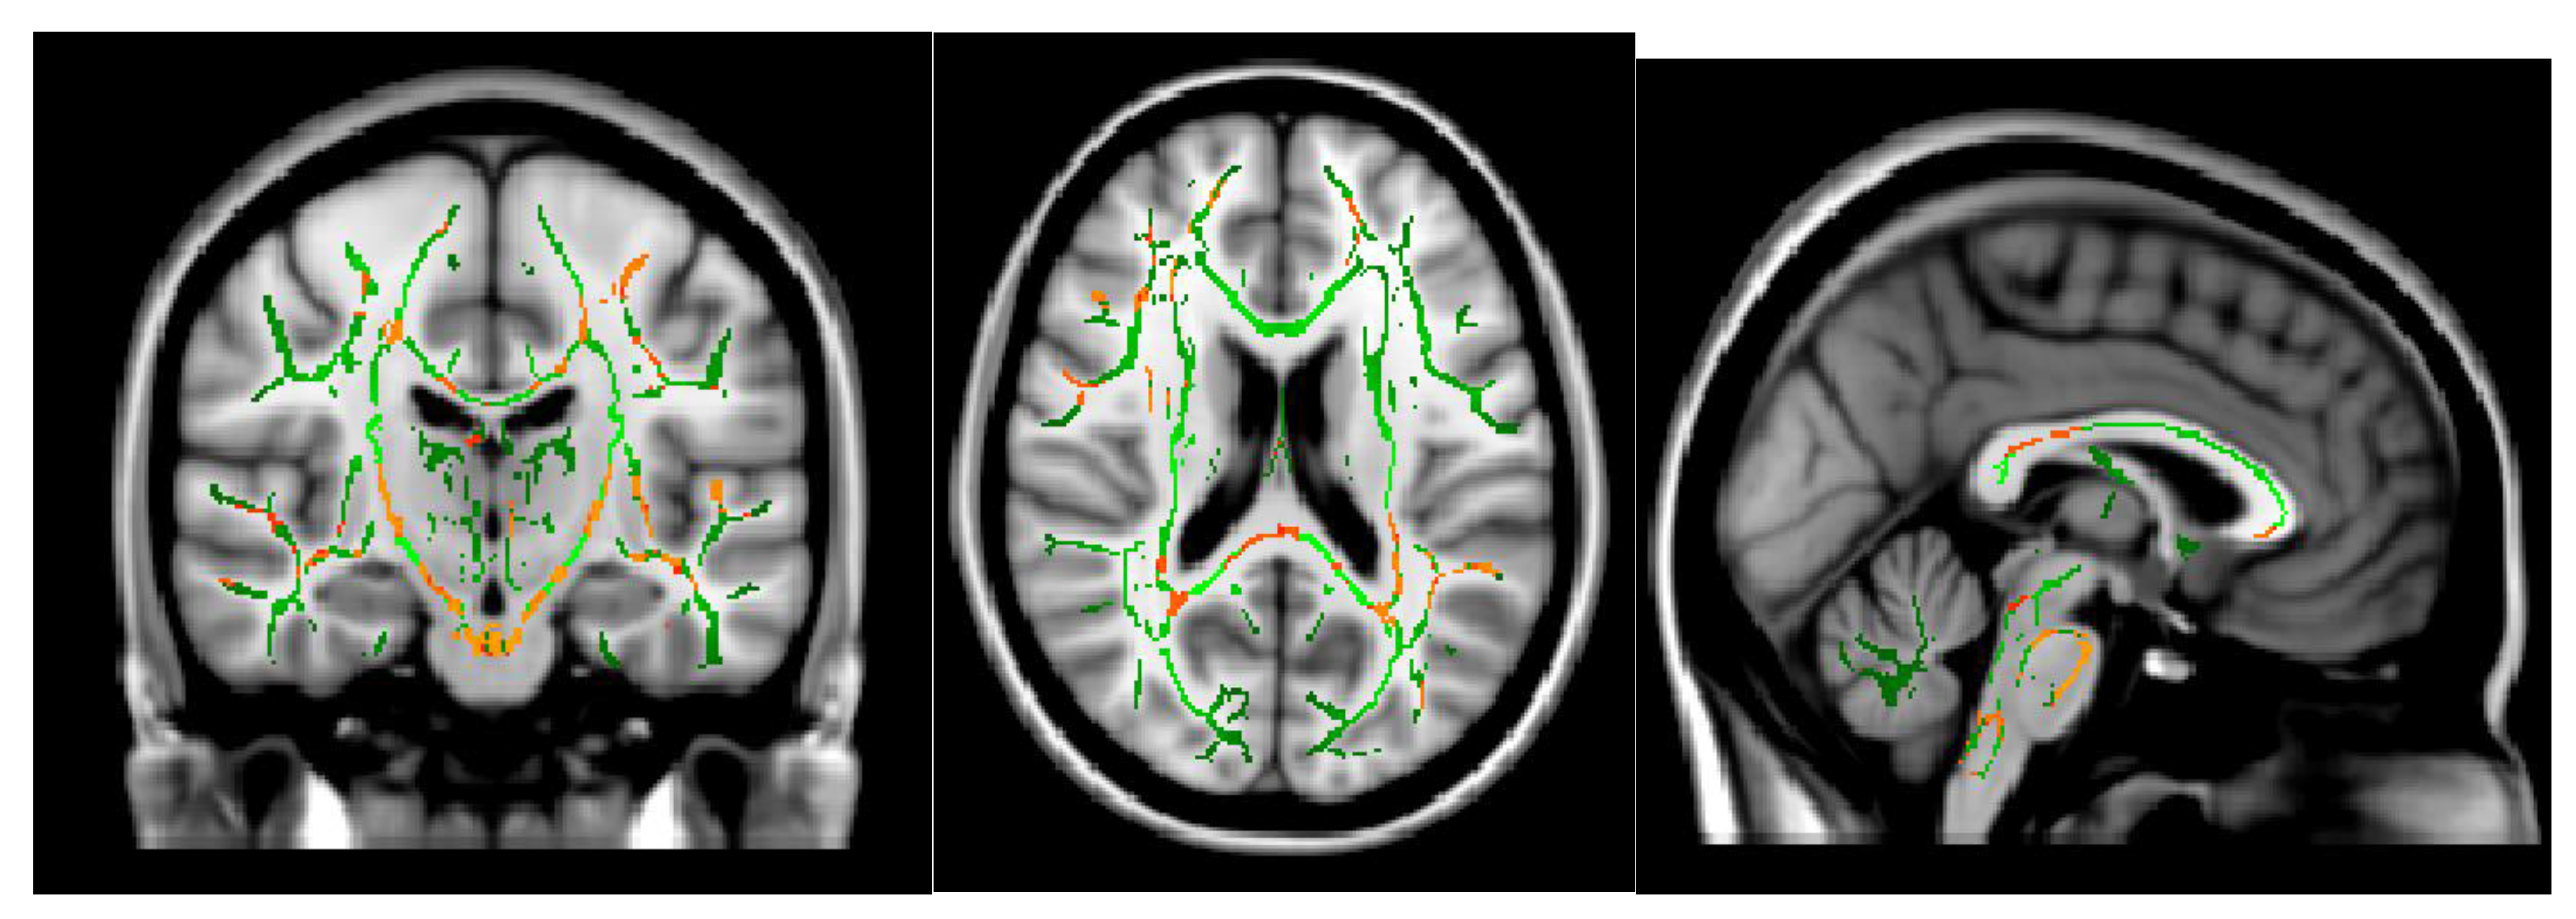

- Shibata, Y.; Ishiyama, S.; Matsushita, A. White matter diffusion abnormalities in migraine and medication overuse headache: A 1.5-Tesla tract-based spatial statistics study. Clin. Neurol. Neurosurg. 2018, 174, 167–173. [Google Scholar] [CrossRef]

- Smith, S.M. Tract-based spatial statistics. NeuroImage 2006, 31, 1487–1505. [Google Scholar] [CrossRef]